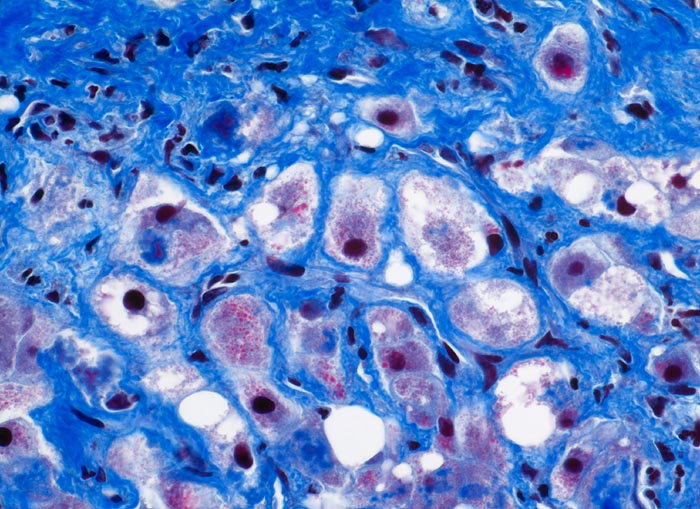

AP/ Floride alkoholische Steatohepatitis

Floride alkoholische Steatohepatitis

Leber